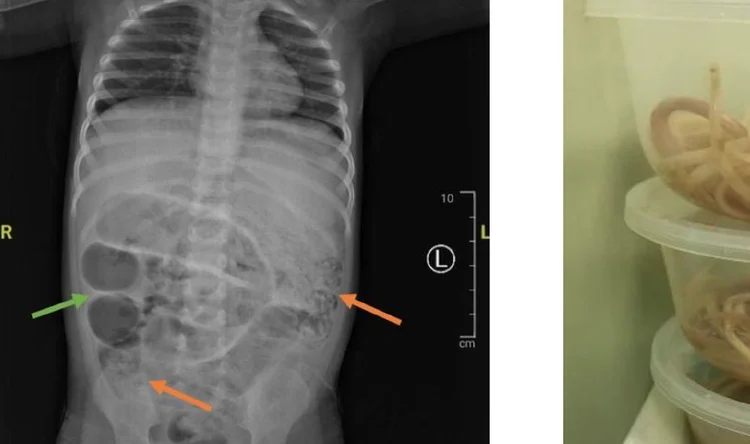

“Cacing gelang atau dikenal dengan nama ilmiah Ascaris lumbricoides, termasuk golongan Nematoda usus. Cacing ini merupakan salah satu jenis cacing STH yang paling sering menginfeksi manusia,” papar Vella Rabu (16/04/2025).

Infeksi Ascaris lumbricoides dapat menimbulkan gangguan kesehatan yang serius terutama jika menyerang anak-anak, seperti menyebabkan gangguan pencernaan yang dapat berujung pada gangguan pola pertumbuhan, anemia dan kekurangan gizi.